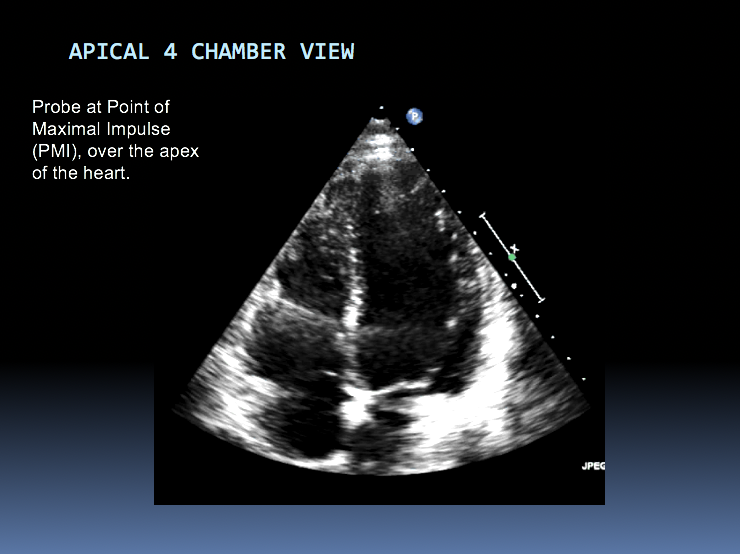

Identify the chambers shown in this image: